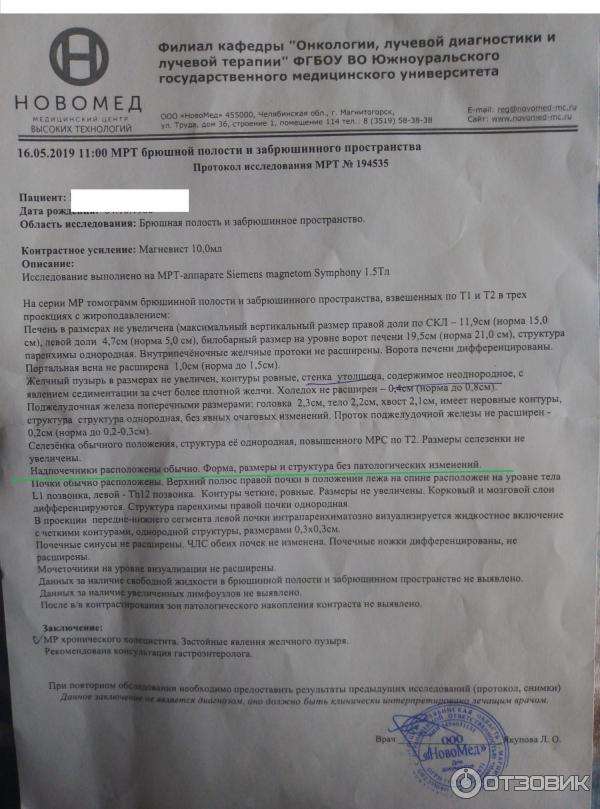

Методы динамического контрастирования печени на МРТ

Раздел: Снимки-подсказки